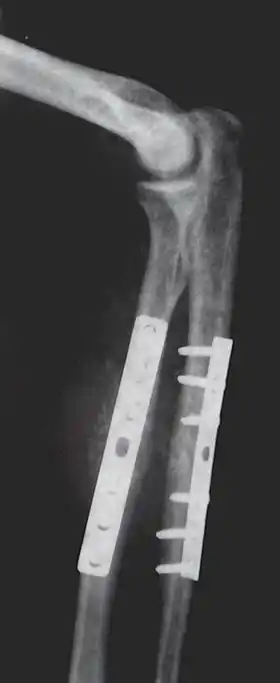

- Repair fracture of radius (bone)/ulna

Advances made in surgical technique during the 18th century, such as John Hunter's research on tendon healing and Percival Pott's work on spinal deformity steadily increased the range of new methods available for effective treatment. Robert Chessher, a pioneering British orthopedist, invented the double-inclined plane, used to treat lower-body bone fractures, in 1790.[6] Antonius Mathijsen, a Dutch military surgeon, invented the plaster of Paris cast in 1851. Until the 1890s, though, orthopedics was still a study limited to the correction of deformity in children. One of the first surgical procedures developed was percutaneous tenotomy. This involved cutting a tendon, originally the Achilles tendon, to help treat deformities alongside bracing and exercises. In the late 1800s and first decades of the 1900s, significant controversy arose about whether orthopedics should include surgical procedures at all.